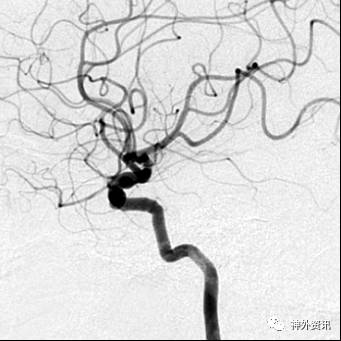

病例一

眼动脉动脉瘤,支架完全释放后,微导管成袢逆行到位

病例二

眼动脉动脉瘤,支架释放前,微导管成袢逆行到位

病例三

A1起始段动脉瘤,微导管成袢逆行到位

病例四

海绵窦区硬脑膜动静脉瘘,海绵窦下外侧干超选栓塞